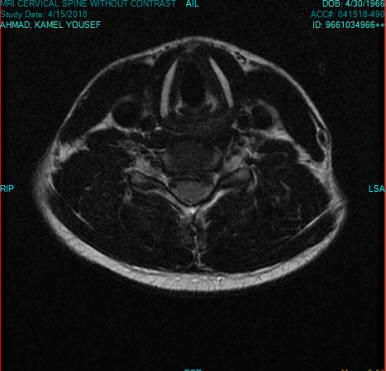

23-MAY-2018  TAMER MUSTAFA AL-SHAHAYBEH  31 YEARS  HUGE EXTRUDED DISC C5-6 WITH LEFT FORAMINAL OCCLUSION.

The patient came to the clinic 08-April-2018 complaining of neck pain for 5 month with left upper limb pain with numbness of the thumb of the left hand. The patient performed MRI cervical spine 26-December-2017 showing extruded disc C5-6 with left foraminal occlusion.

On examination; the patient has severe pain when turning the head to all sides, more when turning to the right. There is weak flexion and extension of the left hand 4/5 and left triceps 4/5. There is hypalgesia of the thumb of the left hand.

The patient was sent for investigation and MRI cervical spine performed 15-April-2018 showing the same extrusion. Lab investigations and dynamic studies were normal. The MRI investigation was done under the name of Ahmad Kamel Yousef for financial reasons.

Saggital and axial views of the extrusion.